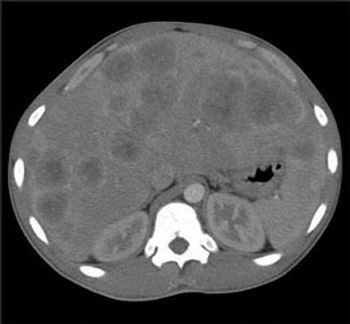

Right upper quadrant pain of 24 hours’ duration prompted a 20-year-old man with a history of gastritis to seek medical attention. The pain was sharp and nonradiating, with no alleviating or aggravating factors. The patient occasionally consumed alcohol and regularly smoked cigarettes (tobacco and marijuana). He denied nausea, vomiting, diarrhea, and diaphoresis. Right upper quadrant pain of 24 hours’ duration prompted a 20-year-old man with a history of gastritis to seek medical attention. The pain was sharp and nonradiating, with no alleviating or aggravating factors.